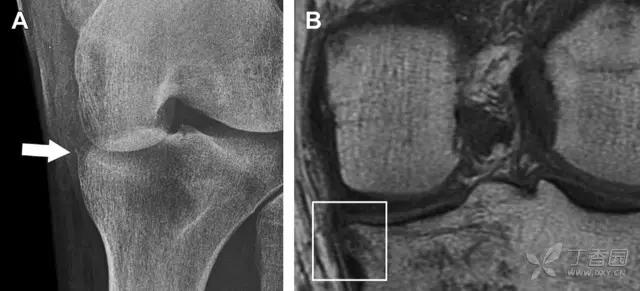

8. Segond 骨折和反向 Segond 骨折

(1)Segond 骨折

是发生在胫骨平台外侧的垂直撕脱性骨折。这种骨折在前后位 X 线片上显示最佳。屈曲位时膝关节受到内旋*力暴**作用,导致皮质骨撕脱性骨折,这种骨折常发生在运动员身上。

常引起股骨内髁和胫骨平台后内侧骨挫伤,75%~100% 的患者伴前交叉韧带断裂,33% 的患者伴外侧半月板损伤。

一位足球运动员的 Segond 骨折。A 正位片示关节线下方胫骨外侧皮质撕脱(箭头)。B MRI 冠状位 T1 加权像示附着于髂胫带的骨折碎片(空箭头)(来源:Radiol Clin N Am 53 (2015) 737–755,YU,Ohio)

(2)反向 Segond 骨折

胫骨平台内侧皮质骨撕脱性骨折,被称为内侧 Segond 骨折或反向 Segond 骨折。这种骨折的旋转机制与 Segond 骨折相反,该骨折与后交叉韧带断裂及内侧半月板损伤相关。

一位足球运动员的反向 Segond 骨折。A 正位片示关节线处的胫骨内侧见一细小骨折片(箭头)。B MRI 冠状位 T1 加权像示骨折片出现在内侧副韧带关节囊附着处(方框)(来源:Radiol Clin N Am 53 (2015) 737–755,YU,Ohio)